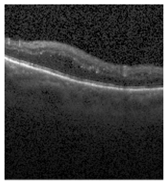

The publicly accessible dataset [27] encompasses detailed cross-sectional images of living patients’ retinas, which have been classified into four distinct categories: Normal, CNV, Drusen, and DME. These categories are visually represented in Figure 3. The dataset comprises a grand total of 84,492 images, distributed as follows: CNV contains 37,457 images, Normal contains 26,567 images, DME includes 11,600 images, and Drusen encompasses 8868 images.

Figure 3. Illustrative examples from the retinal image dataset are presented. Figure (a) showcasing Choroidal NeoVascularization, characterized by the presence of neovascular membranes (indicated by white arrowheads) along with associated sub-retinal fluid (marked by arrows). Figure (b) illustrates Diabetic Macular Edema, which manifests as intra-retinal fluid associated with retinal thickening (denoted by arrows). Figure (c) displays multiple instances of drusen (highlighted by arrowheads), while Figure (d) illustrates a normal, pristine retina with an undisturbed foveal structure and no signs of retinal fluid or edema.